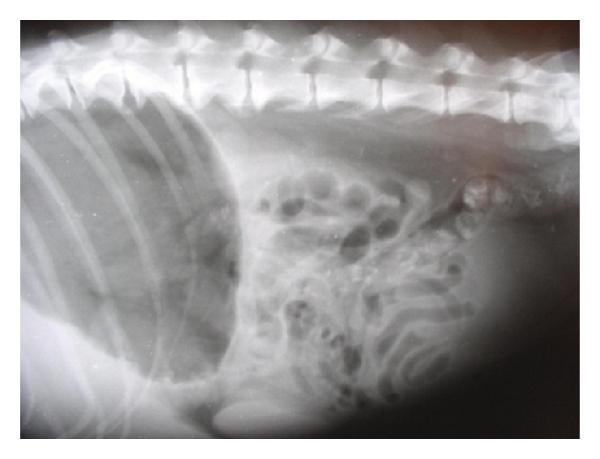

Hepatic disease is often treatable and has a predictable prognosis when a definitive diagnosis is made. The aim of clinicopathological evaluation of hepatobiliary affections is to identify and characterize hepatic damage and dysfunction, identify possible primary causes of secondary liver disease, differentiate causes of icterus, evaluate potential anaesthetic risks, assess prognosis and response to xenobiotics, and monitor response to therapy. This paper describes the different diagnostic methods and imaging techniques employed in diagnosis of hepatobiliary affections in dogs. Besides reviewing the significant clinical manifestations and imaging structural abnormalities in diagnostic approach to different hepatic affections, it also depicts radiographic, ultrasonographic, and wherever applicable, the laparoscopic characterization of different hepatic affections and target lesions encountered in clinical cases presented in the Teaching Veterinary Clinical Complex, COVAS, Palampur in the year 2007-2008.

肝病通常是可治疗的,一旦做出明确诊断,其预后是可预测的。肝胆疾病临床病理评估的目的是识别和描述肝损伤及功能障碍,确定继发性肝病可能的主要病因,鉴别黄疸的病因,评估潜在的麻醉风险,评估预后及对外源化学物质的反应,并监测治疗反应。本文描述了用于诊断犬肝胆疾病的不同诊断方法和成像技术。除了回顾不同肝病诊断方法中的重要临床表现和成像结构异常外,还描述了2007 - 2008年在帕兰普尔兽医临床综合教学中心(COVAS)出现的临床病例中不同肝病及目标病变的放射学、超声学特征,以及在适用情况下的腹腔镜特征。